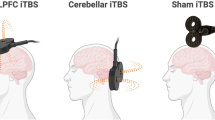

In this work, we shift the focus from structural neuroplasticity to functional neuroplasticity, and from localized analysis to whole-brain analysis. Via the fully automated independent component analysis (ICA) framework [E-Field modeling The Simulation of Non-Invasive Brain Stimulation (SimNIBS) toolbox was used for E-field modeling to generate a subject-specific anatomically realistic volume conductor model [35]. Via a combination of the FSL toolbox and the SPM 12 toolbox, T1- and T2-weighted images were segmented into skin, bone, eyes, cerebral spinal fluid, ventricles, and gray and white matter. The segmented tissue compartments were meshed into a head model using Gmsh, and ECT electrodes were added to the head mesh in either RUL or received BT configuration, stimulated with 600, 700, or 800 mA as per arm assignment. The voltages and electric fields that correspond to the stimulation configuration were calculated throughout the head mesh. Based on the electrode placement (BT or RUL) and the amplitude (600, 700, or 800 mA) from the last treatment of the ECT series, we calculated the whole-brain E-field strength (Ebrain). Ebrain was measured as the 90th percentile of E-field magnitude across the whole brain. Ebrain at 90th percentile is standard based on previous E-field investigations [29, 36]. Ebrain at 90th percentile is strongly correlated with those calculated at other percentiles: 50th (r = 0.95), 75th (r = 0.99), 85th (r = 1.0), and 95th (r = 1.0). The QC resting-state fMRI data were analyzed via the Neuromark framework which provides a robust estimation of functional networks across subjects [ The code of the Neuromark framework and the Neuromark template have been released and integrated into the group ICA Toolbox (GIFT, https://trendscenter.org/software/gift/), which can be downloaded and used directly by users worldwide. Other MATLAB codes of this study can be obtained from the corresponding author. James SL, Abate D, Abate KH, Abay SM, Abbafati C, Abbasi N, et al. Global, regional, and national incidence, prevalence, and years lived with disability for 354 diseases and injuries for 195 countries and territories, 1990–2017: a systematic analysis for the Global Burden of Disease Study 2017. Lancet (Lond, Engl). 2018;392:1789. Otte C, Gold SM, Penninx BW, Pariante CM, Etkin A, Fava M, et al. Major depressive disorder. Nat Rev Dis Prim 2016;2:1–20. Trifu S, Sevcenco A, Stănescu M, Drăgoi A, Cristea M Efficacy of electroconvulsive therapy as a potential first‑choice treatment in treatment‑resistant depression (Review). Exp Ther Med. 2021; 22. https://doi.org/10.3892/etm.2021.10716. Martin D, Katalinic N, Hadzi-Pavlovic D, Ingram A, Ingram N, Simpson B, et al. Cognitive effects of brief and ultrabrief pulse bitemporal electroconvulsive therapy: A randomised controlled proof-of-concept trial. Psychol Med. 2020;50:1121–8. Porter RJ, Baune BT, Morris G, Hamilton A, Bassett D, Boyce P et al. Cognitive side-effects of electroconvulsive therapy: what are they, how to monitor them and what to tell patients. BJPsych Open 2020; 6. https://doi.org/10.1192/bjo.2020.17. Semkovska M, McLoughlin DM. Objective cognitive performance associated with electroconvulsive therapy for depression: A systematic review and meta-analysis. Biol Psychiatry. 2010;68:568–77. Bouckaert F, Sienaert P, Obbels J, Dols A, Vandenbulcke M, Stek M, et al. ECT: Its brain enabling effects: a review of electroconvulsive therapy-induced structural brain plasticity. J ECT. 2014;30:143–51. Fu Z, Sui J, Espinoza R, Narr K, Qi S, Sendi MSE, et al. Whole-brain functional connectivity dynamics associated with electroconvulsive therapy treatment response. Biol Psychiatry Cogn Neurosci Neuroimaging. 2021. https://doi.org/10.1016/j.bpsc.2021.07.004 Wang D, Tian Y, Li M, Dahmani L, Wei Q, Bai T, et al. Functional connectivity underpinnings of electroconvulsive therapy-induced memory impairments in patients with depression. Neuropsychopharmacology. 2020;45:1579–87. Wang J, Wei Q, Wang L, Zhang H, Bai T, Cheng L, et al. Functional reorganization of intra- and internetwork connectivity in major depressive disorder after electroconvulsive therapy. Hum Brain Mapp. 2018;39:1403–11. Menon V. Large-scale brain networks and psychopathology: a unifying triple network model. Trends Cogn Sci. 2011;15:483–506. Li W, Mai X, Liu C. The default mode network and social understanding of others: What do brain connectivity studies tell us. Front Hum Neurosci. 2014; 8. https://doi.org/10.3389/fnhum.2014.00074. Wei Q, Bai T, Chen Y, Ji G, Hu X, **e W et al. The changes of functional connectivity strength in electroconvulsive therapy for depression: a longitudinal study. Front Neurosci. 2018; 12. https://doi.org/10.3389/fnins.2018.00661. Schutter DJLG, van Honk J. An electrophysiological link between the cerebellum, cognition and emotion: Frontal theta EEG activity to single-pulse cerebellar TMS. Neuroimage. 2006;33:1227–31. Schmahmann JD, Caplan D. Cognition, emotion and the cerebellum. Brain. 2006;129:290–2. Schmahmann JD. Disorders of the cerebellum: ataxia, dysmetria of thought, and the cerebellar cognitive affective syndrome. J Neuropsychiatry Clin Neurosci. 2004;16:367–78. Dep** MS, Wolf ND, Vasic N, Sambataro F, Hirjak D, Thomann PA, et al. Abnormal cerebellar volume in acute and remitted major depression. Prog Neuro-Psychopharmacol Biol Psychiatry. 2016;71:97–102. Xu LY, Xu FC, Liu C, Ji YF, Wu JM, Wang Y et al. Relationship between cerebellar structure and emotional memory in depression. Brain Behav. 2017; 7. https://doi.org/10.1002/brb3.738. He Y, Wang Y, Chang TT, Jia Y, Wang J, Zhong S, et al. Abnormal intrinsic cerebro-cerebellar functional connectivity in un-medicated patients with bipolar disorder and major depressive disorder. Psychopharmacol (Berl). 2018;235:3187–3200. Ma Q, Zeng LL, Shen H, Liu L, Hu D. Altered cerebellar-cerebral resting-state functional connectivity reliably identifies major depressive disorder. Brain Res. 2013;1495:86–94. Porta-Casteràs D, Cano M, Camprodon JA, Loo C, Palao D, Soriano-Mas C, et al. A multimetric systematic review of fMRI findings in patients with MDD receiving ECT. Prog Neuro-Psychopharmacol Biol Psychiatry. 2021;108:110178. Dep** MS, Nolte HM, Hirjak D, Palm E, Hofer S, Stieltjes B, et al. Cerebellar volume change in response to electroconvulsive therapy in patients with major depression. Prog Neuro-Psychopharmacol Biol Psychiatry. 2017;73:31–35. Wei Q, Ji Y, Bai T, Zu M, Guo Y, Mo Y, et al. Enhanced cerebro-cerebellar functional connectivity reverses cognitive impairment following electroconvulsive therapy in major depressive disorder. Brain Imaging Behav. 2021;15:798–806. Argyelan M, Oltedal L, Deng ZD, Wade B, Bikson M, Joanlanne A, et al. Electric field causes volumetric changes in the human brain. Elife. 2019;8:25. Fridgeirsson EA, Deng ZD, Denys D, van Waarde JA, van Wingen GA. Electric field strength induced by electroconvulsive therapy is associated with clinical outcome. NeuroImage Clin. 2021;30:102581. Lee WH, Deng ZD, Kim TS, Laine AF, Lisanby SH, Peterchev AV. Regional electric field induced by electroconvulsive therapy in a realistic finite element head model: Influence of white matter anisotropic conductivity. Neuroimage. 2012;59:2110–23. Deng ZD, Lisanby SH, Peterchev AV. Effect of anatomical variability on electric field characteristics of electroconvulsive therapy and magnetic seizure therapy: a parametric modeling study. IEEE Trans Neural Syst Rehabil Eng. 2015;23:22–31. Abbott CC, Quinn D, Miller J, Ye E, Iqbal S, Lloyd M, et al. Electroconvulsive therapy pulse amplitude and clinical outcomes. Am J Geriatr Psychiatry. 2021;29:166–78. Deng Z, Argyelan M, Miller J, Quinn D. Electroconvulsive therapy, electric field, neuroplasticity, and clinical outcomes. Mol Psychiatry. 2022;27:1676–82. Du Y, Fu Z, Sui J, Gao S, **ng Y, Lin D et al. NeuroMark: an automated and adaptive ICA based pipeline to identify reproducible fMRI markers of brain disorders. NeuroImage Clin. 2020; 28. https://doi.org/10.1016/j.nicl.2020.102375. Sackeim HA, Prudic J, Devanand DP, Nobler MS, Lisanby SH, Peyser S, et al. A prospective, randomized, double-blind comparison of bilateral and right unilateral electroconvulsive therapy at different stimulus intensities. Arch Gen Psychiatry. 2000;57:425–34. Baron IS. Delis-Kaplan executive function system. Child Neuropsychol. 2004;10:147–52. Swanson J. The Delis-Kaplan executive function system: a review. Can J Sch Psychol. 2005;20:117–28. Youssef NA, Ravilla D, Patel C, Yassa M, Sadek R, Zhang LF, et al. Magnitude of reduction and speed of remission of suicidality for low amplitude seizure therapy (Lap-st) compared to standard right unilateral electroconvulsive therapy: a pilot double-blinded randomized clinical trial. Brain Sci. 2019;9:99. Saturnino GB, Antunes A, Thielscher A. On the importance of electrode parameters for sha** electric field patterns generated by tDCS. Neuroimage. 2015;120:25–35. Lee WH, Lisanby SH, Laine AF, Peterchev AV. Minimum electric field exposure for seizure induction with electroconvulsive therapy and magnetic seizure therapy. Neuropsychopharmacology. 2017;42:1192–1200. Fu Z, Iraji A, Sui J, Calhoun VD. Whole-brain functional network connectivity abnormalities in affective and non-affective early phase psychosis. Front Neurosci. 2021; 15. https://doi.org/10.3389/fnins.2021.682110. Tu Y, Fu Z, Mao C, Falahpour M, Gollub RL, Park J et al. Distinct thalamocortical network dynamics are associated with the pathophysiology of chronic low back pain. Nat Commun. 2020; 11. https://doi.org/10.1038/s41467-020-17788-z. Fu Z, Sui J, Turner JA, Du Y, Assaf M, Pearlson GD et al. Dynamic functional network reconfiguration underlying the pathophysiology of schizophrenia and autism spectrum disorder. Hum Brain Mapp. 2020; hbm.25205. Fu Z, Iraji A, Turner JA, Sui J, Miller R, Pearlson GD et al. Dynamic state with covarying brain activity-connectivity: On the pathophysiology of schizophrenia. Neuroimage 2021; 224. https://doi.org/10.1016/j.neuroimage.2020.117385. Stern Y, Gurland B, Tatemichi TK, Tang MX, Wilder D, Mayeux R. Influence of education and occupation on the incidence of Alzheimer’s disease. JAMA J Am Med Assoc. 1994;271:1004–10. Stern Y. What is cognitive reserve? Theory and research application of the reserve concept. J Int Neuropsychol Soc. 2002;8:448–60. Cheng W, Rolls E, Gong W, Du J, Zhang J, Zhang XY, et al. Sleep duration, brain structure, and psychiatric and cognitive problems in children. Mol Psychiatry. 2021;26:3992–4003. Wager TD, Davidson ML, Hughes BL, Lindquist MA, Ochsner KN. Prefrontal-subcortical pathways mediating successful emotion regulation. Neuron. 2008;59:1037–50. Lim SL, Padmala S, Pessoa L. Segregating the significant from the mundane on a moment-to-moment basis via direct and indirect amygdala contributions. Proc Natl Acad Sci USA. 2009;106:16841–6. Petrik D, Lagace DC, Eisch AJ. The neurogenesis hypothesis of affective and anxiety disorders: are we mistaking the scaffolding for the building? Neuropharmacology. 2012;62:21–34. Scott BW, Wojtowicz JM, Burnham WMI. Neurogenesis in the dentate gyrus of the rat following electroconvulsive shock seizures. Exp Neurol. 2000;165:231–6. Boldrini M, Fulmore CA, Tartt AN, Simeon LR, Pavlova I, Poposka V, et al. Human hippocampal neurogenesis persists throughout aging. Cell Stem Cell. 2018;22:589–.e5. Nogueira AB, Nogueira AB, Veiga JCE, Teixeira MJ. Letter: human hippocampal neurogenesis drops sharply in children to undetectable levels in adults. Neurosurgery. 2018;83:E133–E137. Abbott CC, Jones T, Lemke NT, Gallegos P, McClintock SM, Mayer AR, et al. Hippocampal structural and functional changes associated with electroconvulsive therapy response. Transl Psychiatry. 2014;4:e483–e483. Van Den Bossche MJA, Emsell L, Dols A, Vansteelandt K, De Winter FL, Van, et al. Hippocampal volume change following ECT is mediated by rs699947 in the promotor region of VEGF. Transl Psychiatry. 2019;9:1–7. Nordanskog P, Dahlstrand U, Larsson MR, Larsson EM, Knutsson L, Johanson A. Increase in hippocampal volume after electroconvulsive therapy in patients with depression: a volumetric magnetic resonance imaging study. J ECT. 2010;26:62–67. Takamiya A, Chung JK, Liang KC, Graff-Guerrero A, Mimura M, Kishimoto T. Effect of electroconvulsive therapy on hippocampal and amygdala volumes: systematic review and meta-analysis. Br J Psychiatry. 2018;212:19–26. Gbyl K, Videbech P. Electroconvulsive therapy increases brain volume in major depression: a systematic review and meta-analysis. Acta Psychiatr Scand. 2018;138:180–95. Chen F, Madsen TM, Wegener G, Nyengaard JR. Repeated electroconvulsive seizures increase the total number of synapses in adult male rat hippocampus. Eur Neuropsychopharmacol. 2009;19:329–38. Perrin JS, Merz S, Bennett DM, Currie J, Steele DJ, Reid IC, et al. Electroconvulsive therapy reduces frontal cortical connectivity in severe depressive disorder. Proc Natl Acad Sci USA. 2012;109:5464–8. Jonckheere J, Deloulme J, Dall’Igna G, Stimulation NC-B, 2018 undefined. Short-and long-term efficacy of electroconvulsive stimulation in animal models of depression: The essential role of neuronal survival. Elsevier https://www.sciencedirect.com/science/article/pii/S1935861X18302845 (accessed 19 May 2022). Small SA, Schobel SA, Buxton RB, Witter MP, Barnes CA. A pathophysiological framework of hippocampal dysfunction in ageing and disease. Nat Rev Neurosci. 2011;12:585–601. Mueller KD, Koscik RL, LaRue A, Clark LR, Hermann B, Johnson SC, et al. Verbal fluency and early memory decline: results from the Wisconsin registry for Alzheimer’s prevention. Arch Clin Neuropsychol. 2015;30:448–57. Sang L, Qin W, Liu Y, Han W, Zhang Y, Jiang T, et al. Resting-state functional connectivity of the vermal and hemispheric subregions of the cerebellum with both the cerebral cortical networks and subcortical structures. Neuroimage. 2012;61:1213–25. Leech R, Sharp DJ. The role of the posterior cingulate cortex in cognition and disease. Brain. 2014;137:12–32. Habas C. Functional Connectivity of the Cognitive Cerebellum. Front Syst Neurosci. 2021; 15. https://doi.org/10.3389/fnsys.2021.642225. Cano M, Lee E, Cardoner N, Martínez-Zalacaín I, Pujol J, Makris N, et al. Brain volumetric correlates of right unilateral versus bitemporal electroconvulsive therapy for treatment-resistant depression. J Neuropsychiatry Clin Neurosci. 2019;31:152–8. Sartorius A, Demirakca T, Böhringer A, Clemm von Hohenberg C, Aksay SS, Bumb JM, et al. Electroconvulsive therapy induced gray matter increase is not necessarily correlated with clinical data in depressed patients. Brain Stimul. 2019;12:335–43. Tendolkar I, van Beek M, van Oostrom I, Mulder M, Janzing J, Voshaar RO, et al. Electroconvulsive therapy increases hippocampal and amygdala volume in therapy refractory depression: a longitudinal pilot study. Psychiatry Res - Neuroimaging. 2013;214:197–203. Segi-Nishida E. Exploration of new molecular mechanisms for antidepressant actions of electroconvulsive seizure. Biol Pharm Bull. 2011;34:939–44. Miller J, Jones T, Upston J, Deng Z-D, McClintock SM, Ryman S, et al. Ictal theta power as an electroconvulsive therapy safety biomarker. J ECT. 2022;38:88–94. This work was supported by National Institutes of Health (R01MH118695, R01EB020407, R01MH117107, U01MH111826, and R61MH125126), the National Science Foundation (2112455), the National Institute of Mental Health Intramural Research Program (ZIAMH002955), and the China Natural Science Foundation (82022035). ZF, CCA, SMMcC, and VDC designed the study; ZF and CCA performed the data analysis; ZF, JS, JM, Z-DD, and SMMcC wrote the paper. All authors contributed to the results interpretation and discussion. The authors declare no competing interests. Publisher’s note Springer Nature remains neutral with regard to jurisdictional claims in published maps and institutional affiliations. Open Access This article is licensed under a Creative Commons Attribution 4.0 International License, which permits use, sharing, adaptation, distribution and reproduction in any medium or format, as long as you give appropriate credit to the original author(s) and the source, provide a link to the Creative Commons license, and indicate if changes were made. The images or other third party material in this article are included in the article’s Creative Commons license, unless indicated otherwise in a credit line to the material. If material is not included in the article’s Creative Commons license and your intended use is not permitted by statutory regulation or exceeds the permitted use, you will need to obtain permission directly from the copyright holder. To view a copy of this license, visit http://creativecommons.org/licenses/by/4.0/. Fu, Z., Abbott, C.C., Miller, J. et al. Cerebro-cerebellar functional neuroplasticity mediates the effect of electric field on electroconvulsive therapy outcomes.